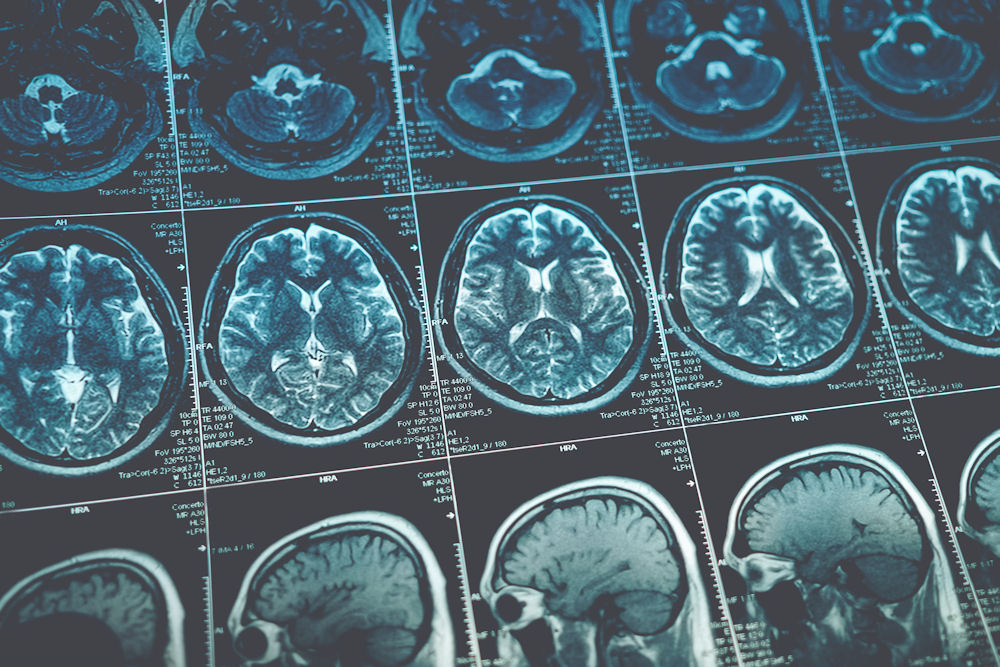

Additionally, the male brain’s reward system plays a critical role in addiction. Men tend to have more receptors in areas of the brain linked to pleasure and reward, making them more sensitive to the effects of substances like drugs and alcohol. When these substances trigger the release of dopamine, the brain experiences an intense pleasure rush, reinforcing the desire to keep using them. Over time, this can lead to tolerance, where more of the substance is needed to achieve the same effect, eventually resulting in addiction.

The connection between stress and addiction is one of the most significant challenges when it comes to understanding the male brain and recovery. Men are often socialized to suppress emotions such as sadness, fear, or vulnerability. Instead of expressing their feelings, they may bottle them up, leading to a buildup of emotional tension. This suppression of emotions can result in chronic stress, which in turn makes them more likely to turn to substances as a way to cope.

Relapse is a common part of the recovery process, and understanding the science behind it can help individuals better prepare for setbacks. According to research, the male brain’s reward system is particularly susceptible to triggers, which can make it more difficult for men to stay on track during recovery. Stress, emotional discomfort, or exposure to substances can trigger a craving, which can lead to a relapse if not properly managed.